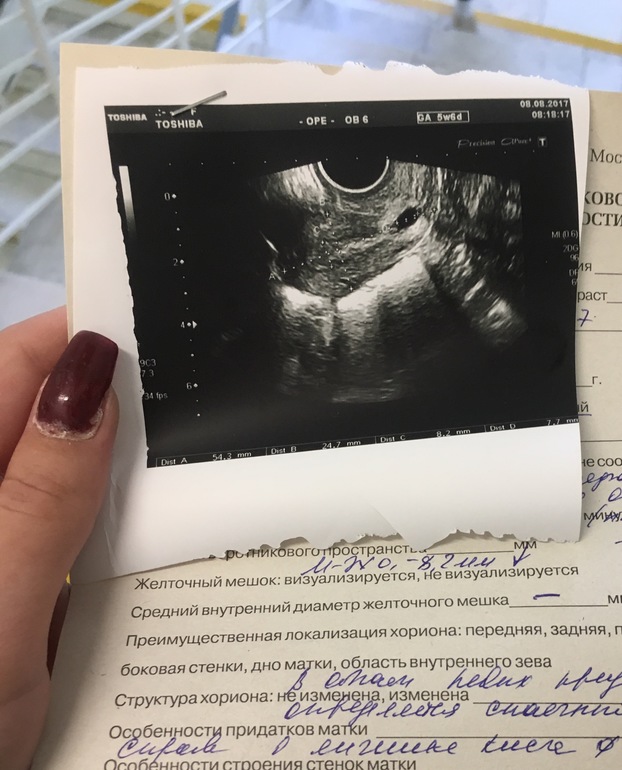

Вопросы про УЗИ, обследования и анализы: что, где, как, когда?Всем привет!По узи беременность 6 недель, плодное яйцо видно на снимках, от зачатия я насчитала 3 недели. Сегодня сдала ХГЧ, по его результатам беременности нет. Узи делала только вчера. У кого так было, что это может быть? Тесты полосат, но не ярко. По идее прикрепление произошло только несколько дней назад, тк были замечены бледнорозовые выделения.

Если 6 недель и уже видно пл.яйцо, то прикрепление никак не неск.дней назад, а недели 1-2 минимум. И хгч у вас беременный, только не на этот срок. Только наблюдать. Удачи!

Пересдайте хгч, вдруг правда ошибка. Или на узи не плодное яйцо, но скорее всего в лаборатории ошиблись. А сколько хгч то показал? По узи беременность со знаком вопроса, это предварительный диагноз